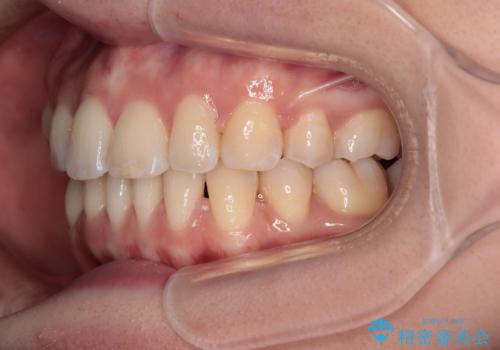

舌の突出癖がなかなか改善されず、上下前歯の接触がやや甘い状態での仕上がりとなりました。

接触が甘い場合、上顎前歯の叢生が後戻りを起こしやすくなるため、治療終了後の保定期間でも舌のトレーニングを継続するように指示しています。